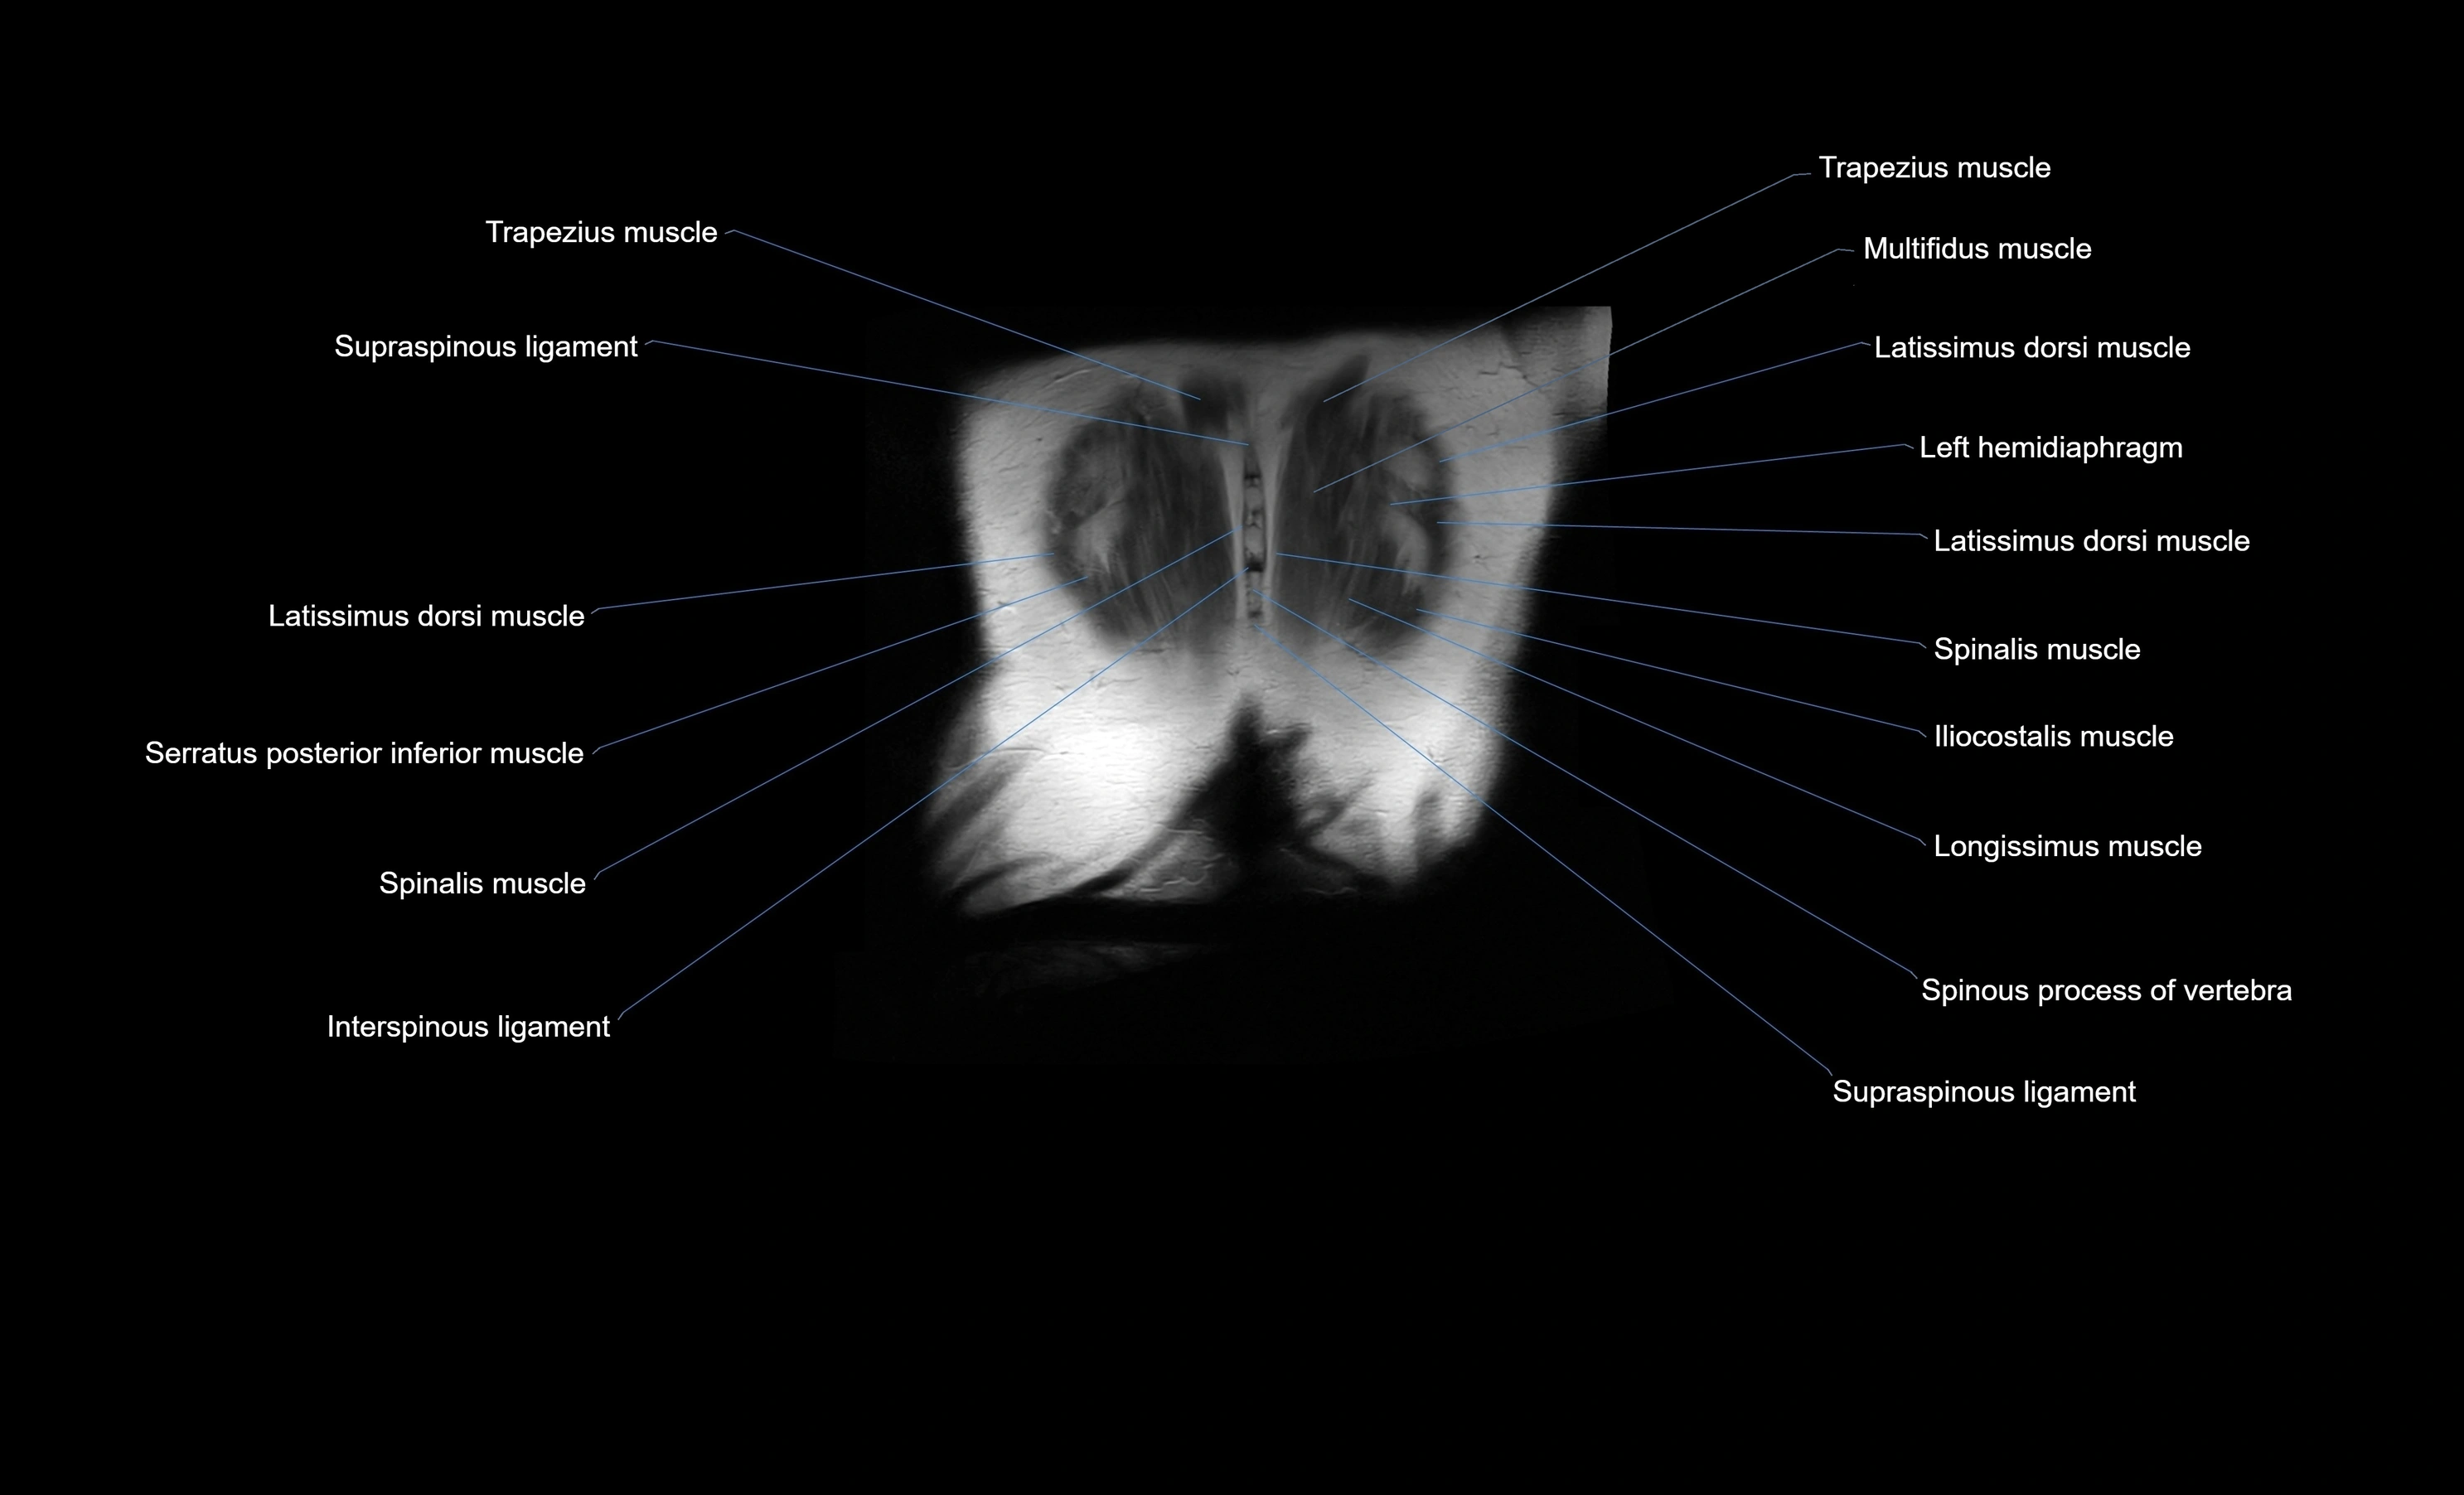

MRI images